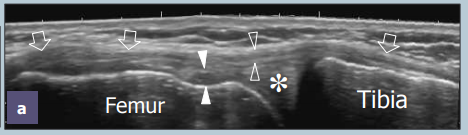

Tendon patellaire